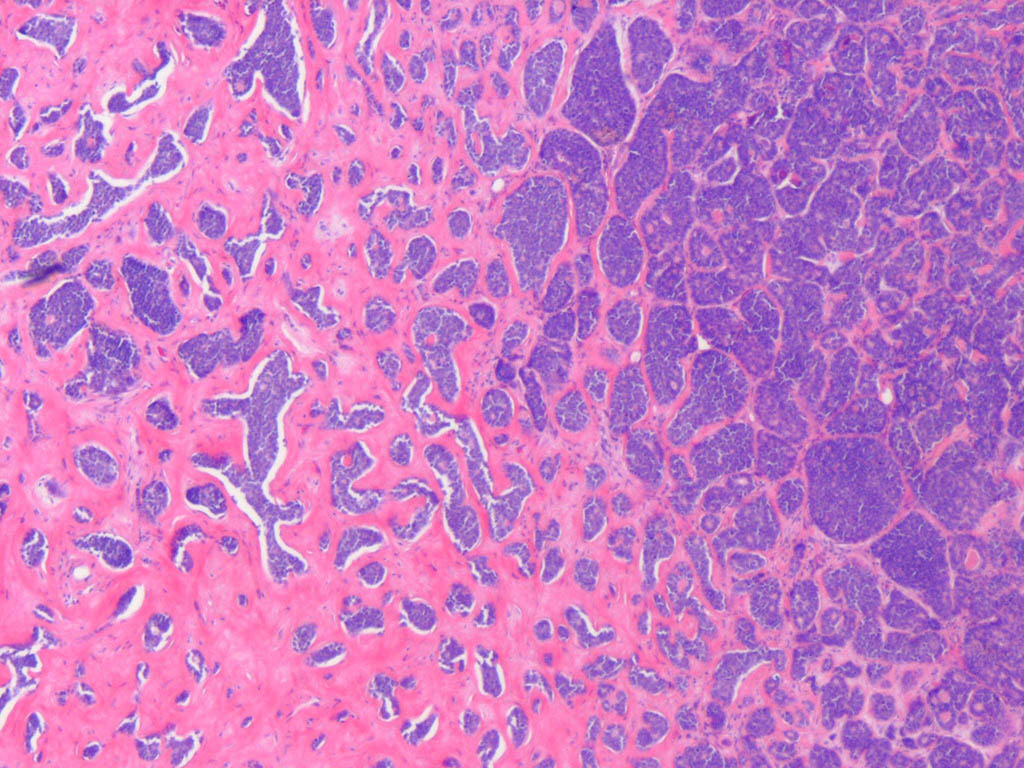

Cylindroma =الأسطوانوم

OLYMPUS DIGITAL CAMERA